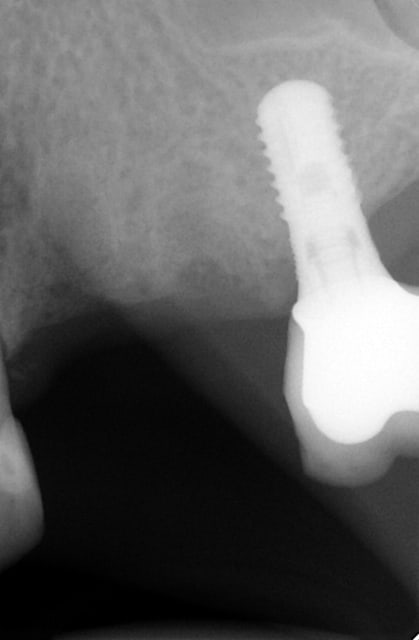

En ce qui concerne la précision, dans ce cas là et pour eviter une augmentation, j ai du placer l implant en mesio palatinal ( voir radio initiale)

En mesurant la hauteur de l os dans le septum ( dans le DVT), celui était seulement de 3 mm. Voilà pourquoi l´implant n est pas dans le septum. L´os a été condensé,la stabilité primaire a donc pu atteindre 50 Ncm.